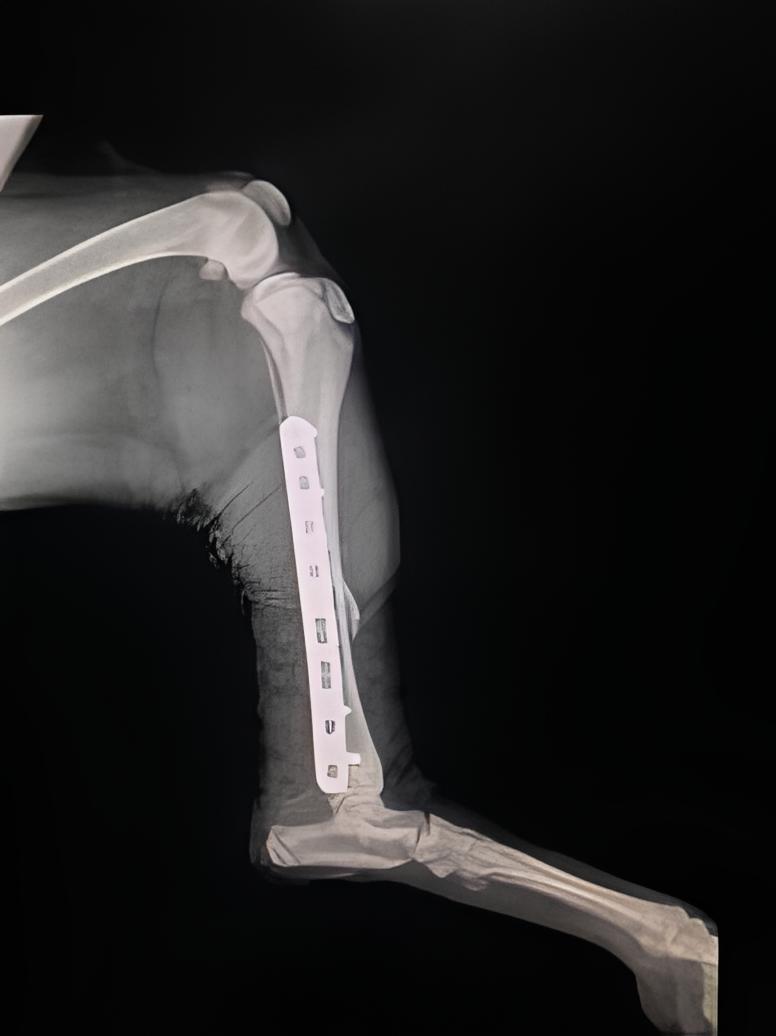

Eles farão exames, possivelmente raio-x, e fornecerão o tratamento adequado, que pode incluir imobilização, medicamentos ou, em alguns casos, cirurgia.